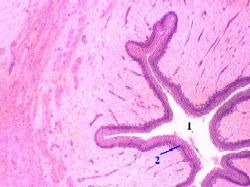

| 3,а-г. Препарат - мочеточник (поперечный срез). Окраска гематоксилин-эозином. | ||

| Просвет и эпителий | а) Просвет (1) мочеточника имеет на поперечном разрезе извилистый (звёздчатый) вид – из-за образования слизистой оболочкой продольных складок. б) К просвету обращён переходный эпителий (2). в) Под ним последовательно располагаются прочие слои стенки: | а-б) Малое увеличение Полный размер |

| Прочие слои стенки | собственная пластинка (3) слизистой оболочки, подслизистая основа (4), мышечная оболочка (5), адвентициальная оболочка (6). | Полный размер |

| Отличия: 1) вид эпителия | Отличия же состоят в следующем. 1) Первый признак - вид эпителия, определяемый по форме ядер самых поверхностных клеток: в мочеточнике они – круглые (переходный эпителий), | в) Мочеточник. Большое увеличение Полный размер |